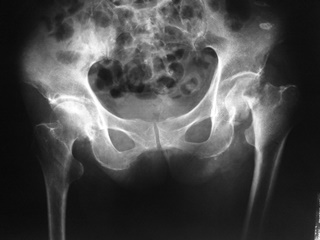

ภาพรังสีแสดงการยุบของกระดูกสันหลังหลายระดับ วิธีการดู คือ จะสังเกตจากความสูงของกระดูกสันหลังเทียบกันในแต่ละระดับ จะพบว่าส่วนของกระดูกสันหลังที่ยุบลงนั้นจะมีความสูง

ของกระดูกสันหลังลดลงเมื่อเทียบกับกระดูกสันหลังที่อยู่ติดกัน